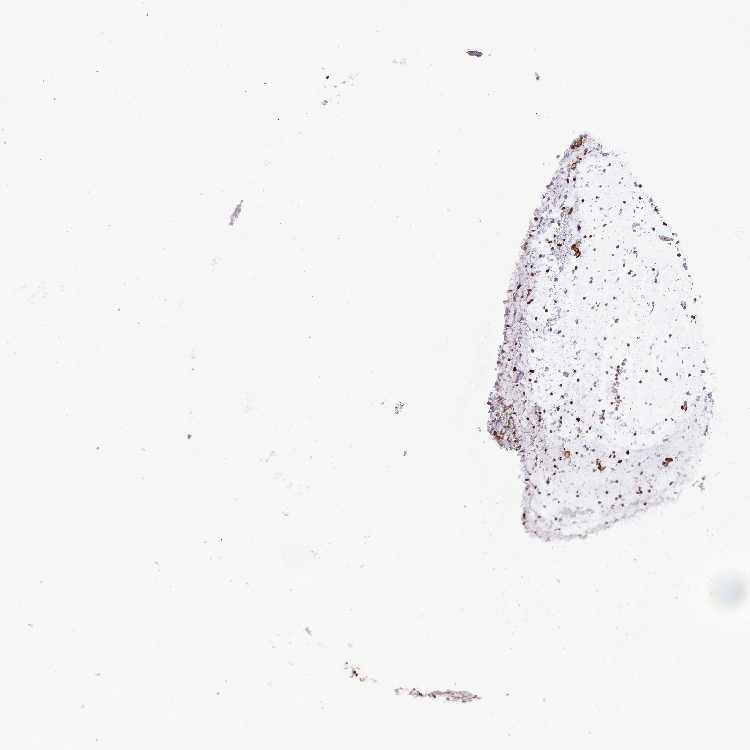

SOFT TISSUE 1 - Antibody stainingi

Antibody staining in the annotated cell types in the current human tissue is reported as not detected, low, medium, or high, based on conventional immunohistochemistry profiling in selected tissues. This score is based on the combination of the staining intensity and fraction of stained cells.

Each image is clickable and will lead to virtual microscopy that enables deeper exploration of all samples and also displays staining intensity scores, fraction scores and subcellular localization as well as patient and tissue information for each sample.

Antibody HPA041667Antibody HPA042093

Fibroblasts Not detectedMedium

Peripheral nerve Not detectedMedium